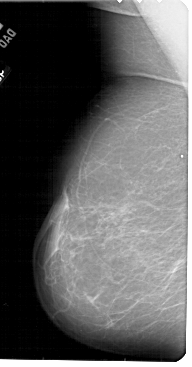

A_1904_1.LEFT_MLO

LEFT_MLO LINES 5491 PIXELS_PER_LINE 2866 BITS_PER_PIXEL 12 RESOLUTION 43.5 NON_OVERLAY